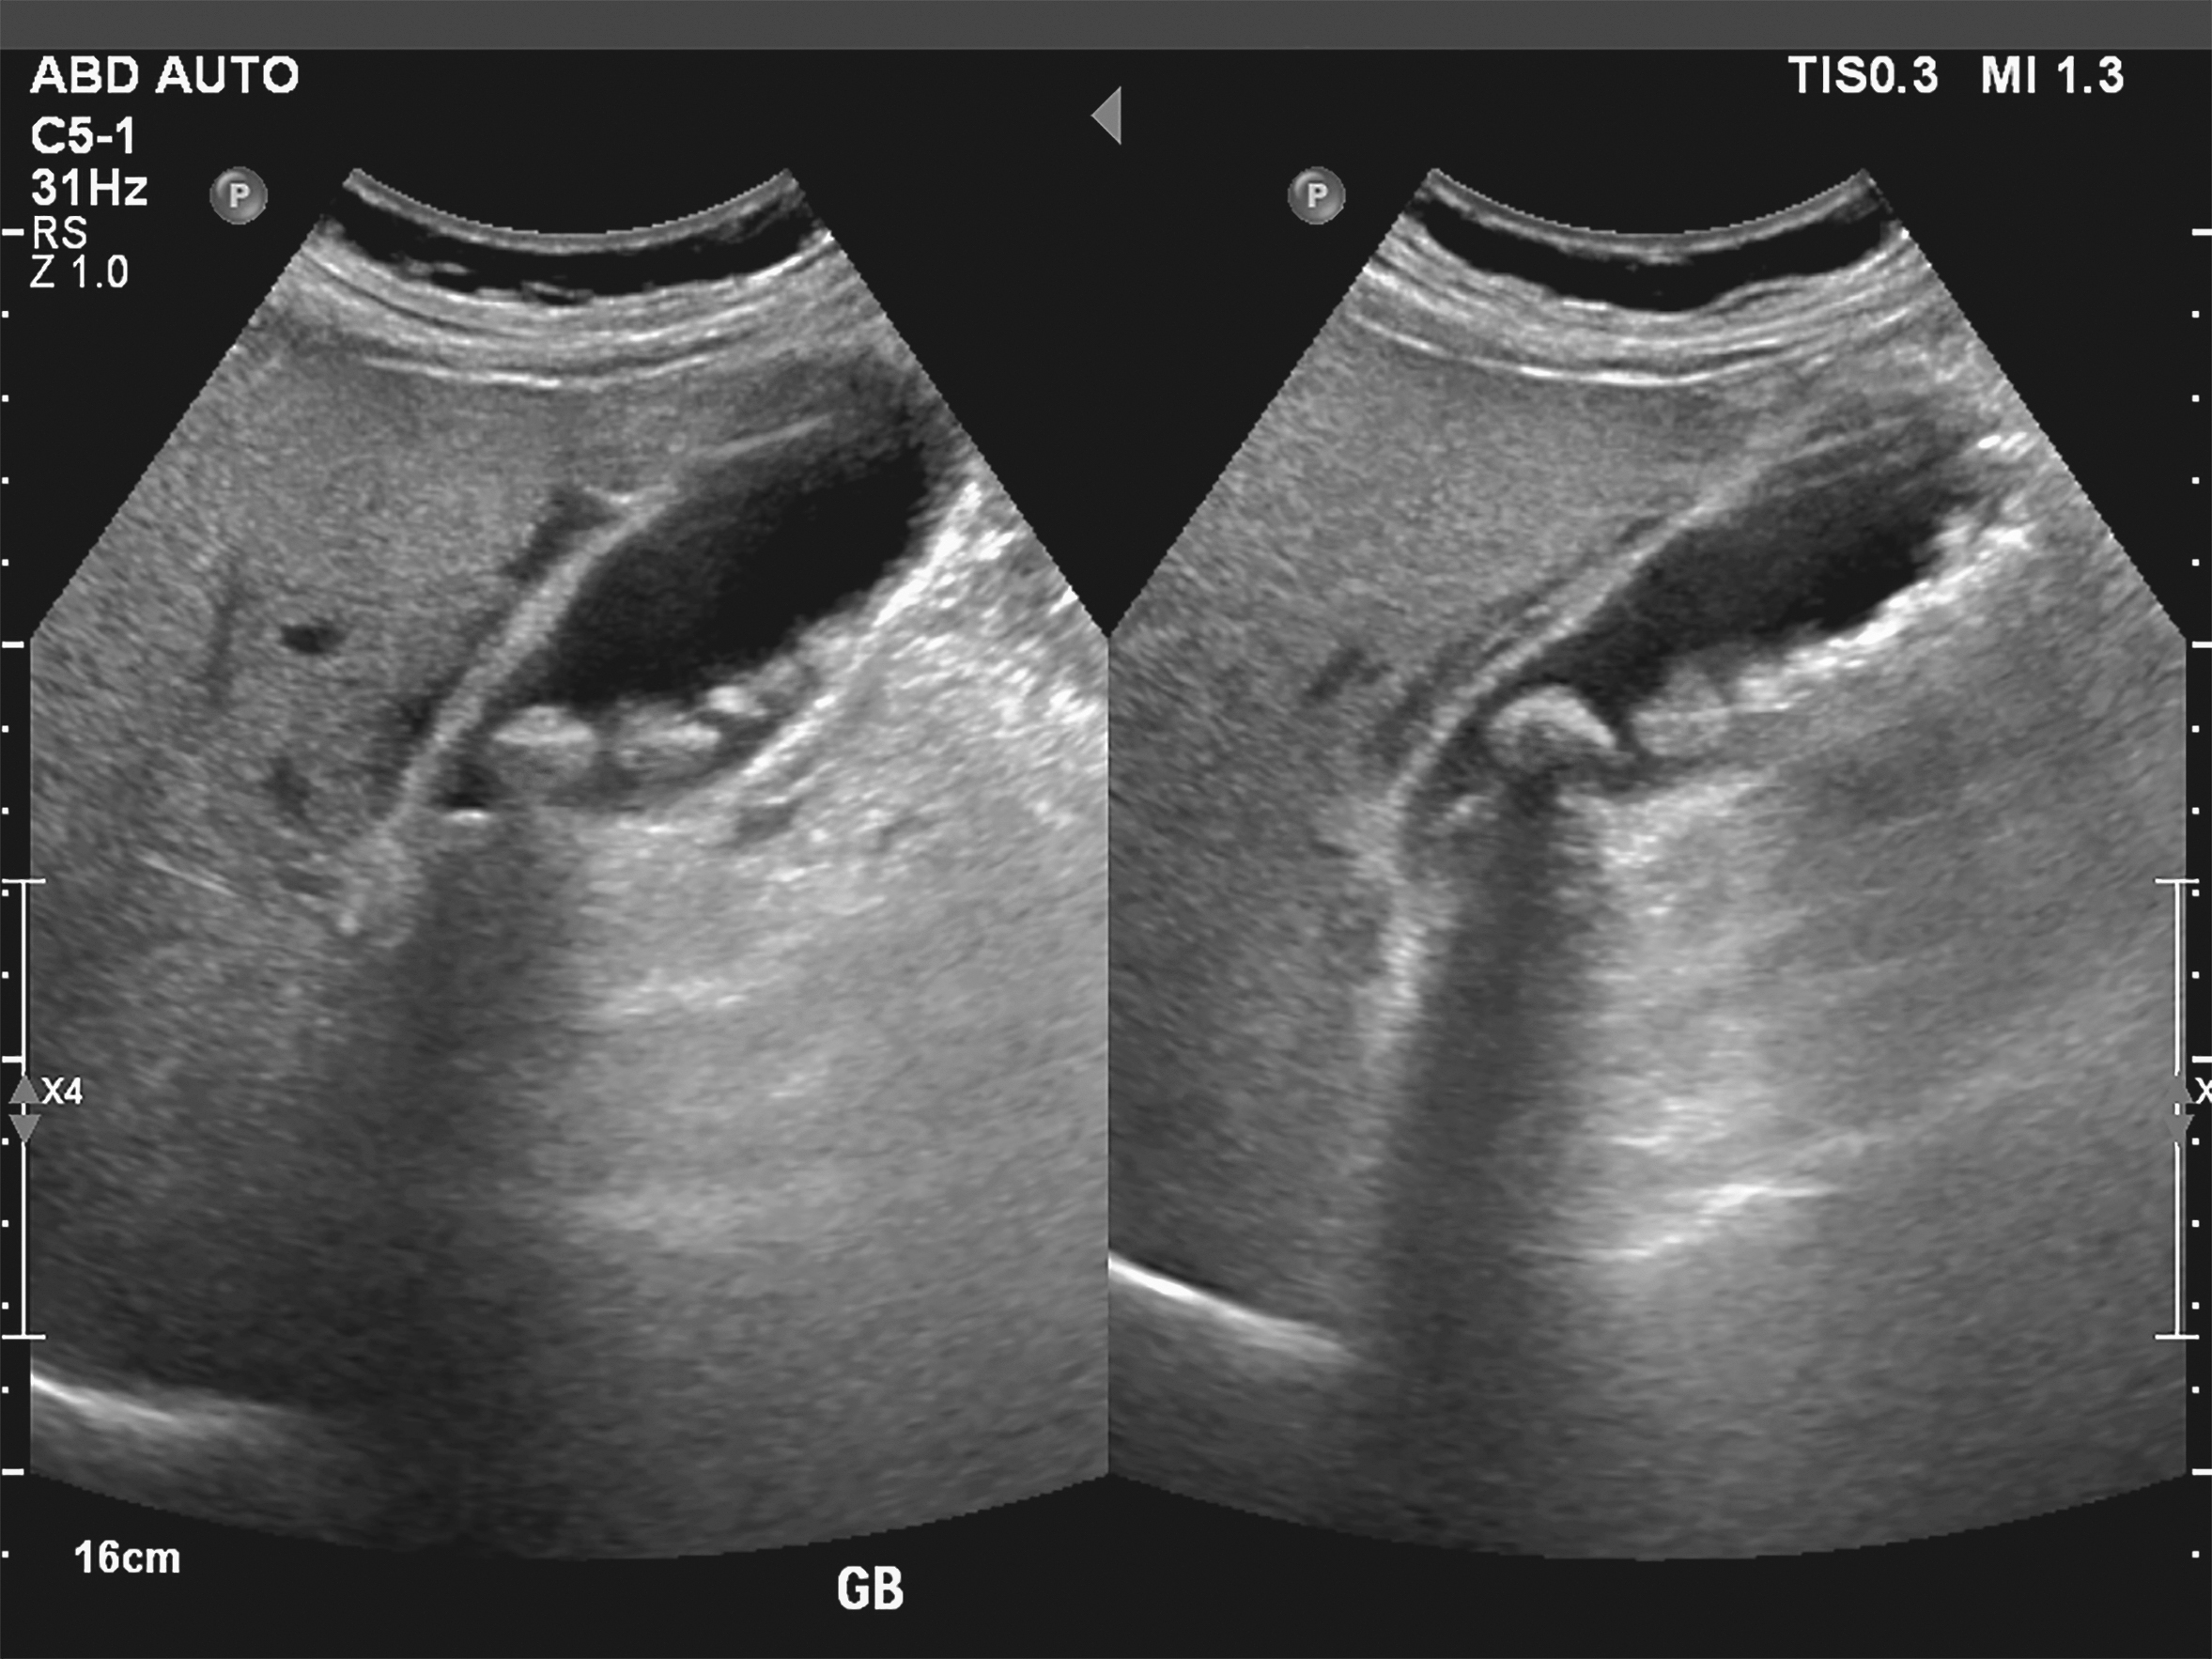

Source: gearwebesb.pages.dev Gallensteine Symptome, Ursachen und Therapie Heilpraxis , Wie erkennt ein Arzt Gallensteine? Ultraschalluntersuchung. Manchmal versperren sie den Gallengang dauerhaft, was im schlimmsten Fall zu schweren.

Source: neprocooqe.pages.dev Gallensteine Schmerzhafte Koliken APOTHEKE ADHOC , Die*der Ärztin*Arzt behandelt die Gallenkolik durch krampflösende Medikamente (Spasmolytika) und starke. Wie erkennt ein Arzt Gallensteine? Ultraschalluntersuchung.